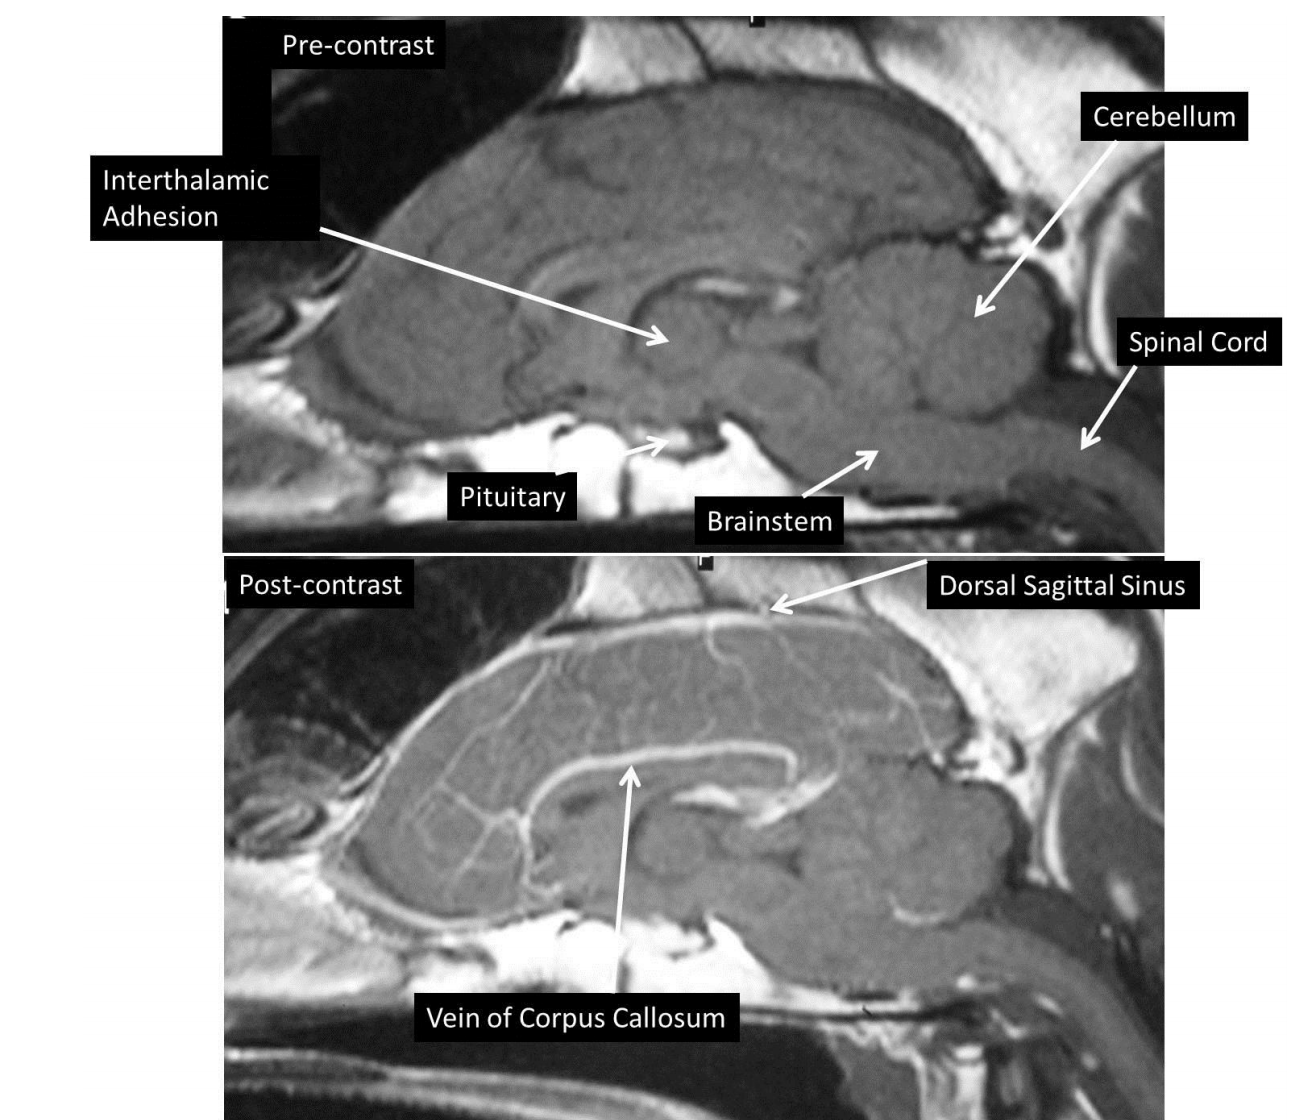

what are these structures and what weight is this scan

T2 weighted scan of the brain and cervical spine

increased signal (hyperintensity) in middle of spinal cord in cervical region –> extending from level of the 2nd cervical vertebra (C2- the axis) well into the thoracic region of the spine

hyperintensity = fluid due to syringomyelia

associated with Chiari-like malformation –> undeveloped caudal fossa of the skull causing compression of the cerebellum and forcing CSF along the central canal of the spinal cord rather than subarachnoid space –> causes dilation of central canal and distortion of the spinal cord

dogs presenting with neck pain or signs of scratching at neck